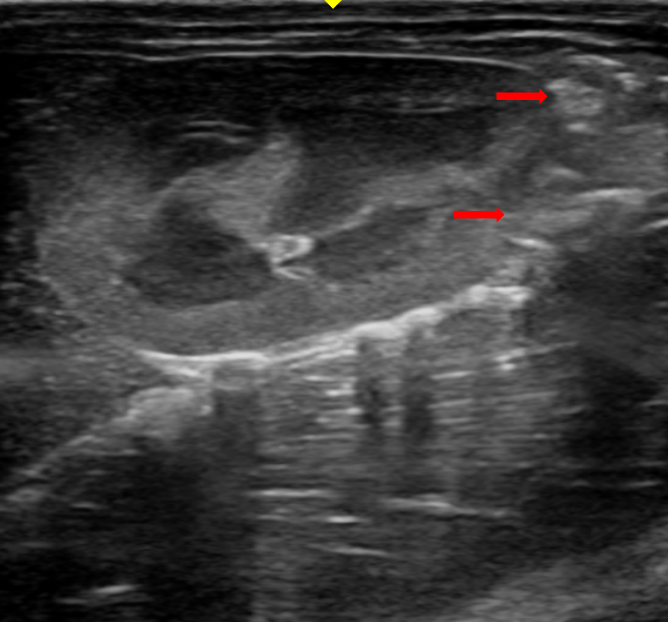

检测手段:术后定期通过超声观察肿瘤生长,典型图像如下(术后 7 天超声图):

[术后 7 天超声追踪图]

注:红色箭头标记为肿瘤占位形态